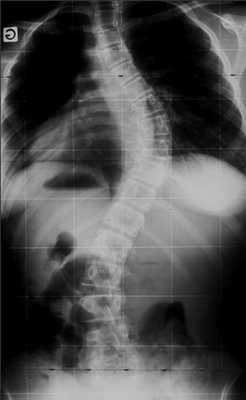

Клинический пример: больная Н., 1999 г.р., прооперированная по поводу сколиотической болезни (рис.1-4):

Рис. 2. Передняя и боковая спондилограмма до операции